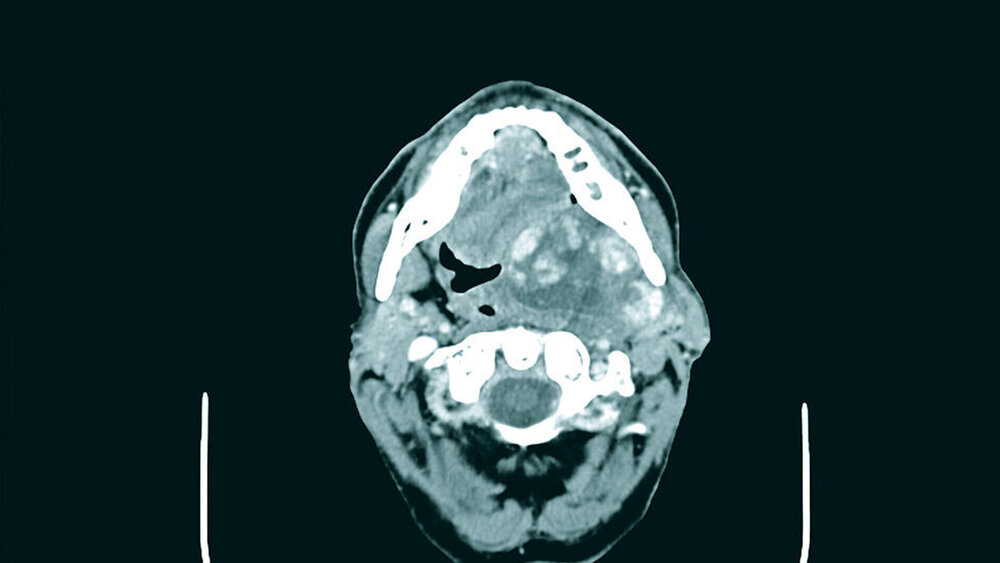

Im Rahmen einer ambulanten Probeentnahme von intra- und extraoral in Lokalanästhesie konnte nur Speicheldrüsengewebe im Sinne einer Sialadenitis mit Sialektasie gewonnen werden, so dass eine erneute Probenentnahme unter stationären Bedingungen von intraoral aus dem Parotistumor und aus dem Bereich der Leukoplakie im vorderen Mundboden erfolgte. Die Ausdehnung des Tumors ist auf den CT-Bildern deutlich zu erkennen (Abbildungen 1 bis 3).